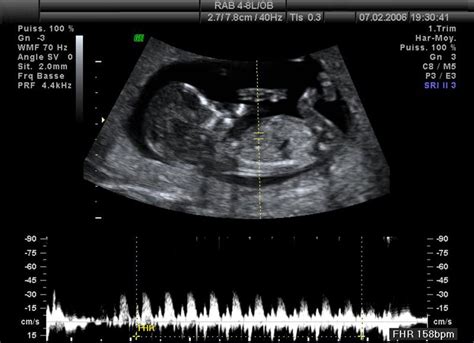

V tomto kritickom období sa dieťa vo vašej maternici stále plne spolieha na placentu, ktorá zabezpečuje prísun výživy a kyslíka, ako aj odvádzanie odpadových látok. Fyzický vývoj pokračuje závratným tempom. V 23. týždni tehotenstva meria bábätko od temena po päty približne 28 až 30 centimetrov. Jeho veľkosť sa dá prirovnať k hlávkovej kapuste alebo k manga. Vzhľadom na jeho vysokú aktivitu a neustále meniace sa polohy v maternici je presné meranie celkovej dĺžky pomocou ultrazvuku často obtiažne. Lekári na určenie približnej dĺžky využívajú špecifické vzorce založené na viacerých čiastkových biometrických mierach, pričom dôležitú úlohu zohráva aj dĺžka stehennej kosti (femuru), ktorá je najdlhšou kosťou u človeka. Je však dôležité si uvedomiť, že tieto hodnoty sú orientačné a môžu sa líšiť kvôli prirodzenej pohyblivosti dieťaťa.

V tomto období je pravdepodobné, že priberáte približne 0,5 kg za týždeň. Kľúčovým ukazovateľom však zostáva veľkosť dieťaťa, ktorú sledujú lekári pomocou ultrazvuku.